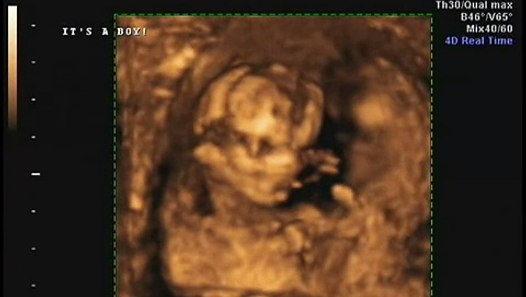

3d Ultrasound 15 Weeks Gender

Early Gender Boys 15 Weeks 3d 4d Hd Ultrasound Virginia